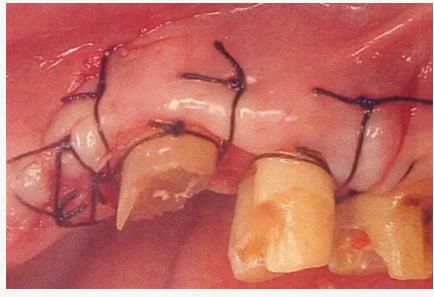

▲圖5-12

使齦瓣上端與牙槽嵴頂一致,通過骨膜縫合進(jìn)行固定。